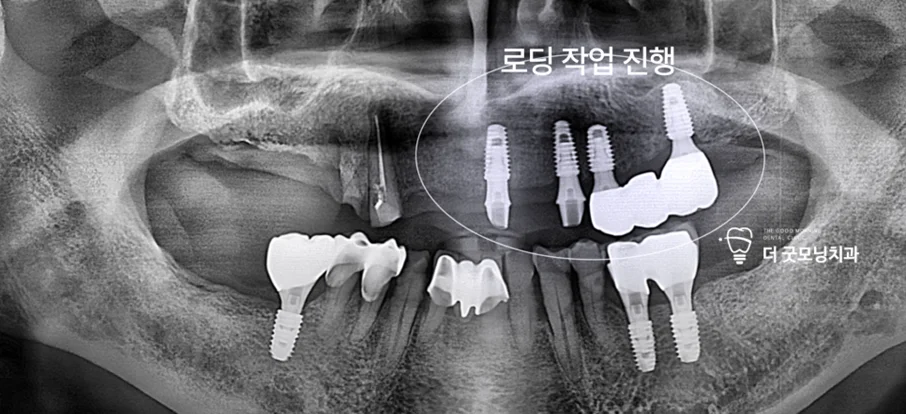

Step 6. 추가 임플란트 식립 — 보험 적용 기간 분리 전략

1년이 경과하여 새로운 보험 적용 기간이 시작되었습니다. 좌측 임플란트의 유착을 확인한 후 로딩 작업을 완료하고, 우측에 4개의 임플란트를 추가 식립했습니다. 이번 수술도 수면마취(의식하 진정) 하에 진행되었습니다.